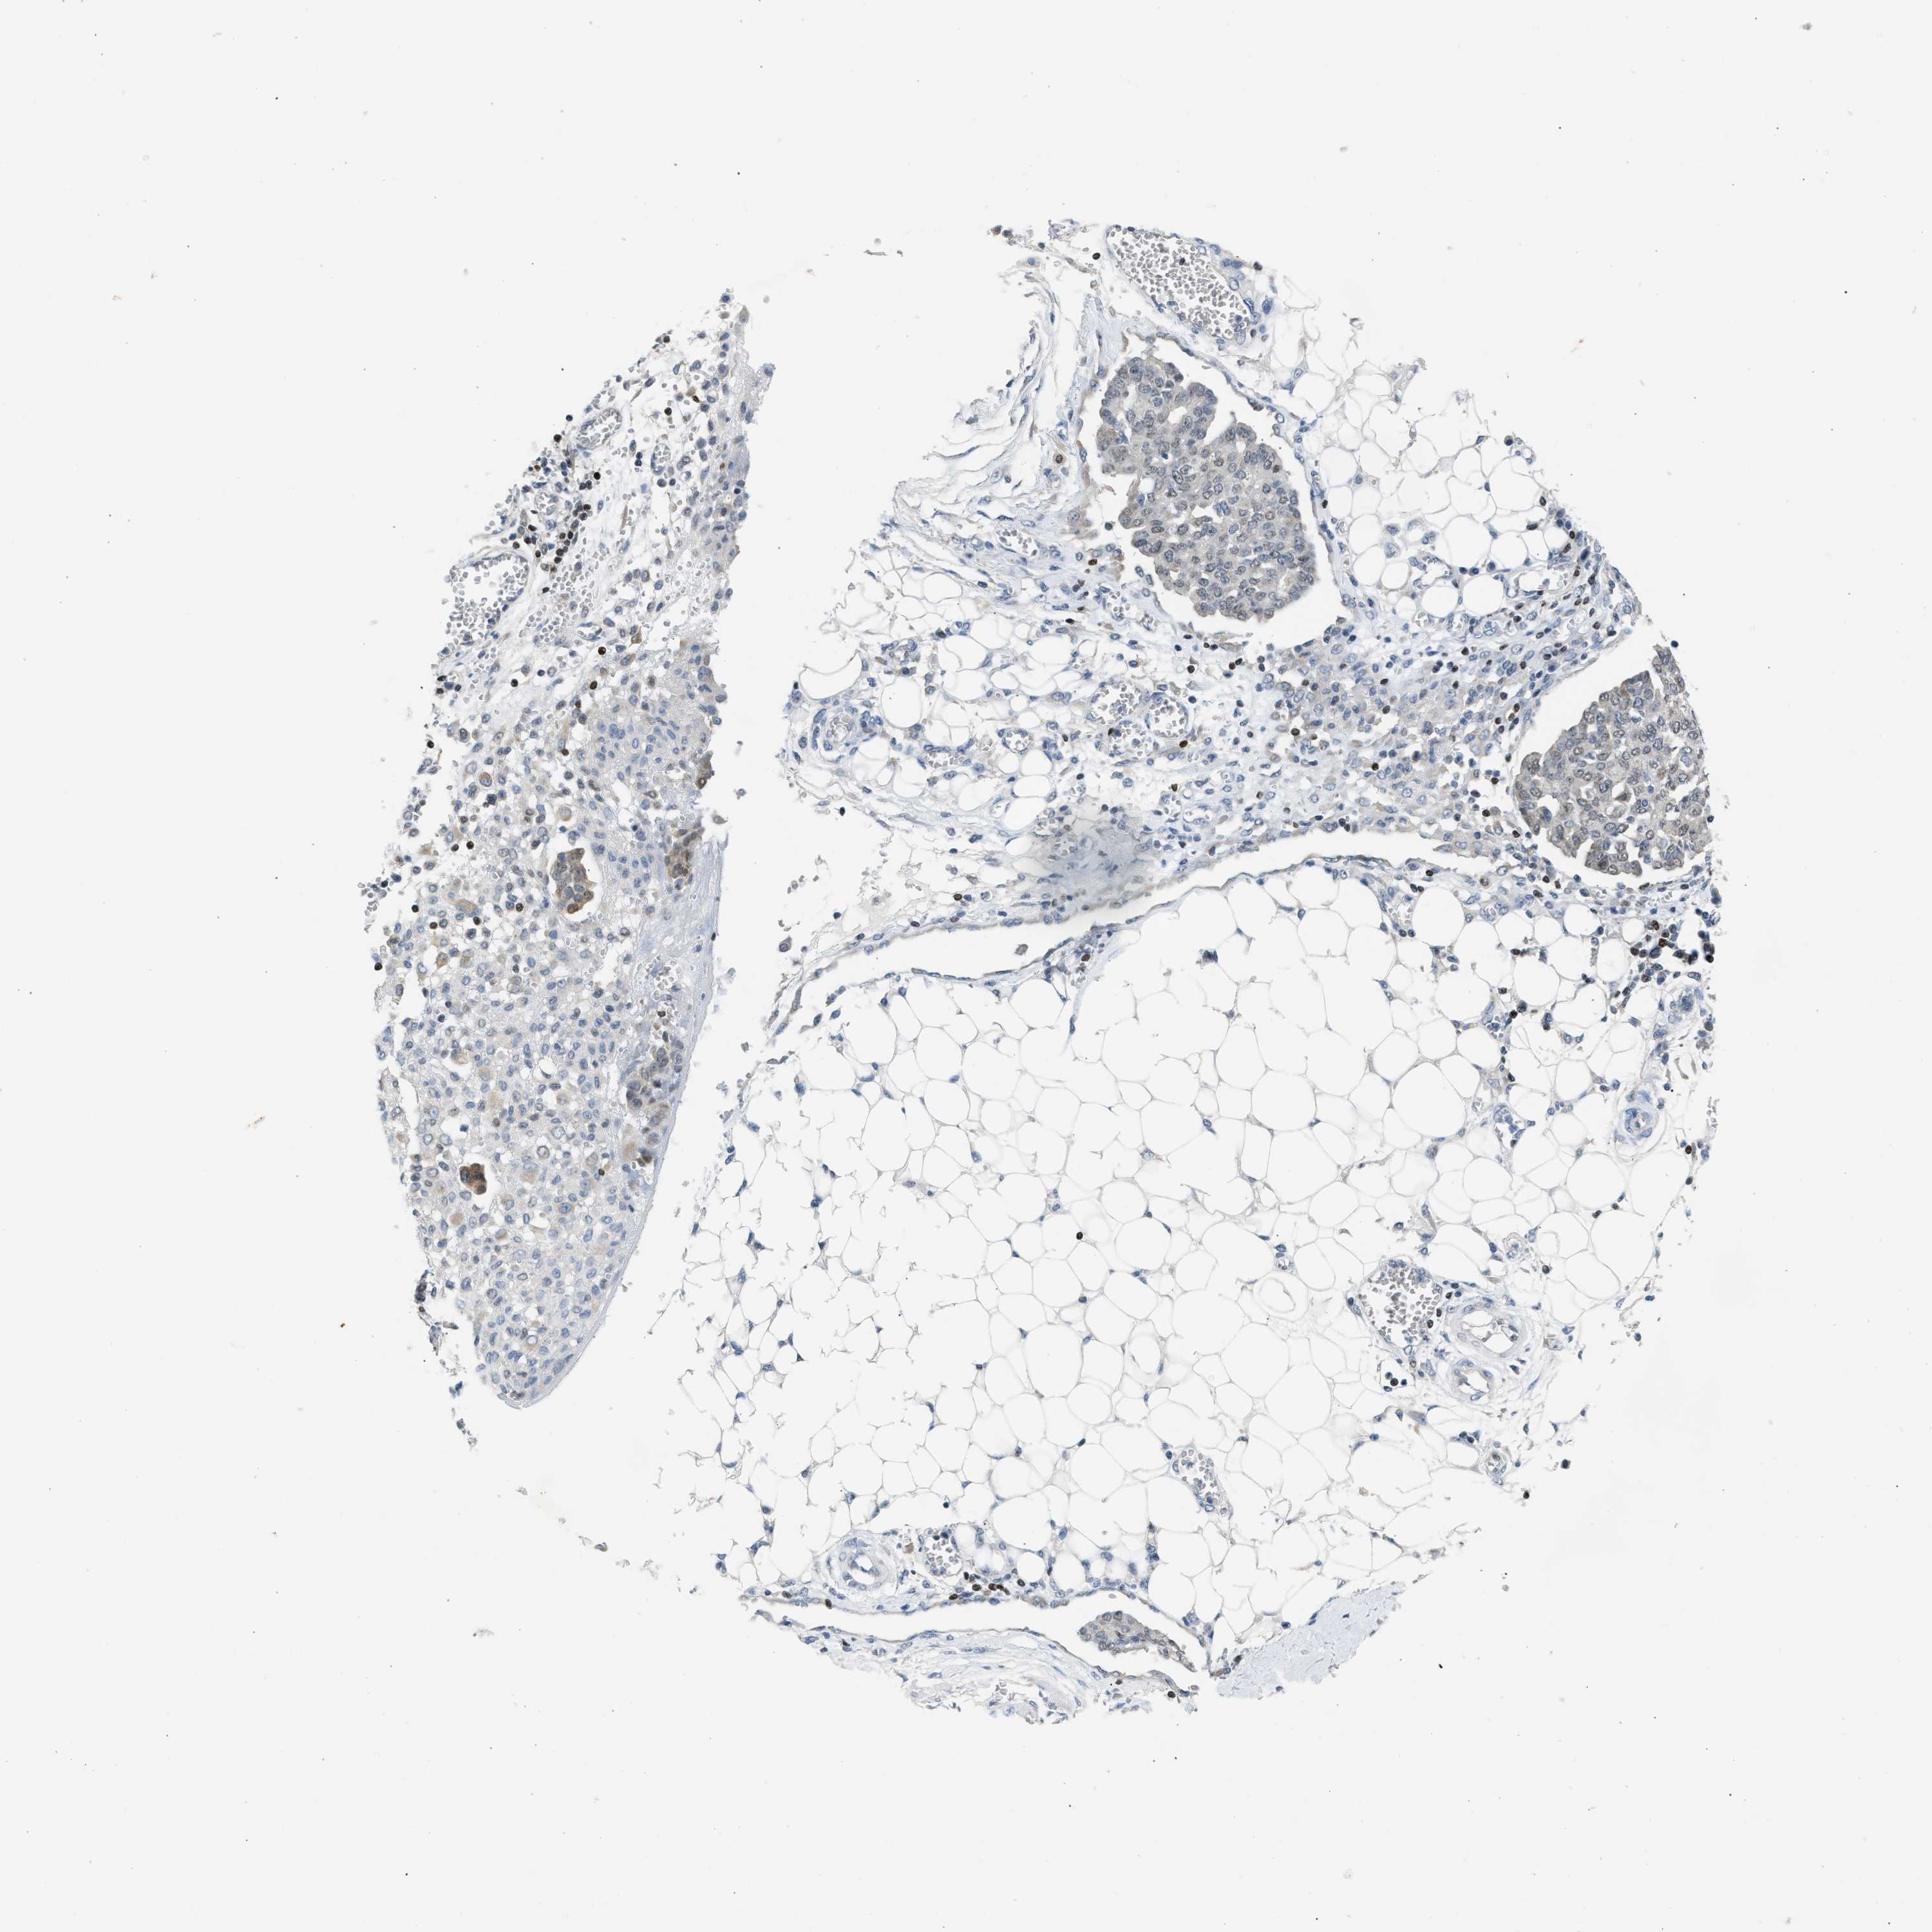

OVARIAN CANCER - Protein expressioni

A mouse-over function shows sample information and annotation data. Click on an image to view it in a full screen mode. Samples can be filtered based on level of antibody staining by selecting one or several of the following categories: high, medium, low and not detected. The assay and annotation is described here.

Note that samples used for immunohistochemistry by the Human Protein Atlas do not correspond to samples in the TCGA dataset.

Antibody stainingi

Antibody staining in the annotated cell types in the current human tissue is reported as not detected, low, medium, or high, based on conventional immunohistochemistry profiling in selected tissues. This score is based on the combination of the staining intensity and fraction of stained cells.

Each image is clickable and will lead to virtual microscopy that enables deeper exploration of all samples and also displays staining intensity scores, fraction scores and subcellular localization as well as patient and tissue information for each sample.

Antibody CAB020139

Staining

High

Medium

Low

Not detected

Intensity

Strong

Moderate

Weak

Negative

Quantity

>75%

75%-25%

<25%

None

Location

Nuclear

Cytoplasmic/membranous

Cytoplasmic/membranous,nuclear

Cystadenocarcinoma, serous, NOS

Carcinoma, endometroid

Cystadenocarcinoma, mucinous, NOS

Carcinoma, NOS